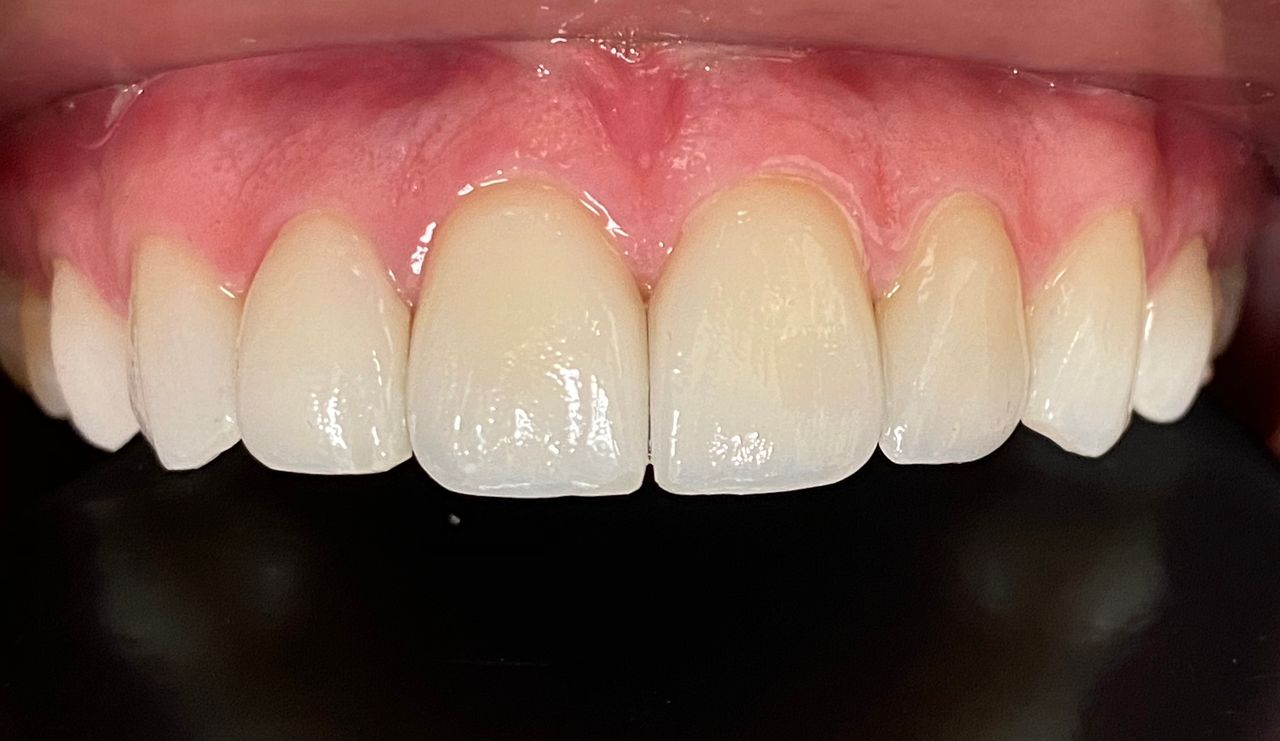

Coronas estéticas

La realización de coronas dentales debe ser exclusivamente por un experto.La corona dental da protección y estética a un diente, no siempre requiere de tratamiento de endodoncia, solo en algunas ocasiones. El procedimiento requiere de mucha precisión para lograr una corona dental perfectamente bien sellada, de acuerdo a los mas recientes artículos científicos 8 de 10 coronas no sellan a la perfección.Anteriormente se realizaban coronas de metal con porcelana las cuales al cabo de un tiempo cambiaban de color y presentaban corrosión en el diente, en la actualidad contamos con diversos tipos de coronas realizadas por medio de CAD CAM zirconia, porcelana y otros materiales de alta calidad.

Diseño de sonrisa

Una alternativa inovadora para cambiar la forma y color de dientes es mediante el sistema U Venner de carillas de porcelana o de ceromero. Previamente se requiere de fotografías intraorales, toma de moldes dentales y toma de color dental. Excelente opción para diseñar una nueva sonrisa.